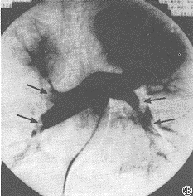

3 瘀點

發生在大約50%-60%的病人中,常在傷後24-48h內出現。在病人的兩側腋部、胸部前外側、頸前部、臍周、結膜和口腔黏膜等處出現。瘀點的解剖學基礎與大腦、肺等其他有病理生理過程的受累器官所觀察到的相似,通過顯微檢查顯示脂肪滴正阻塞毛細血管,並且被小血管周圍出血所包圍。